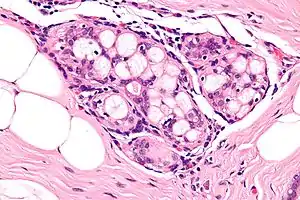

It is important to correctly identify, as it can be confused with atypical ductal hyperplasia, cribriform ductal carcinoma in situ (DCIS), and adenoid cystic carcinoma.[1]

Collagenous spherulosis is characterized by a tubular/cribriform architecture with intratubular eosinophilic material that classically is arranged like the spokes of a wheel ("radial spikes"). There is usually no mitotic activity, and two cells populations (epithelial & myoepithelial) are present, like in benign breast glands.

The lesions are typically small (less than 50 spherules per lesion, less than 100 micrometers in size) and may be multifocal.